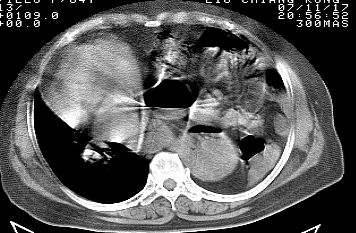

标题: CT10753:女, 64岁 隔疝 [打印本页]

标题: CT10753:女, 64岁 隔疝

女, 64岁 三十年前胸部外伤史, 间断胸闷,

典型左侧膈疝,疝出物为胃和大网膜,纵隔右移

同意左侧膈疝,不过,有过外伤史,左肺有受压征象,同时有胸膜增厚。

30年了,病人够痛苦的了,应该做修补术。

左侧隔疝(创伤性?),与外伤关系大。